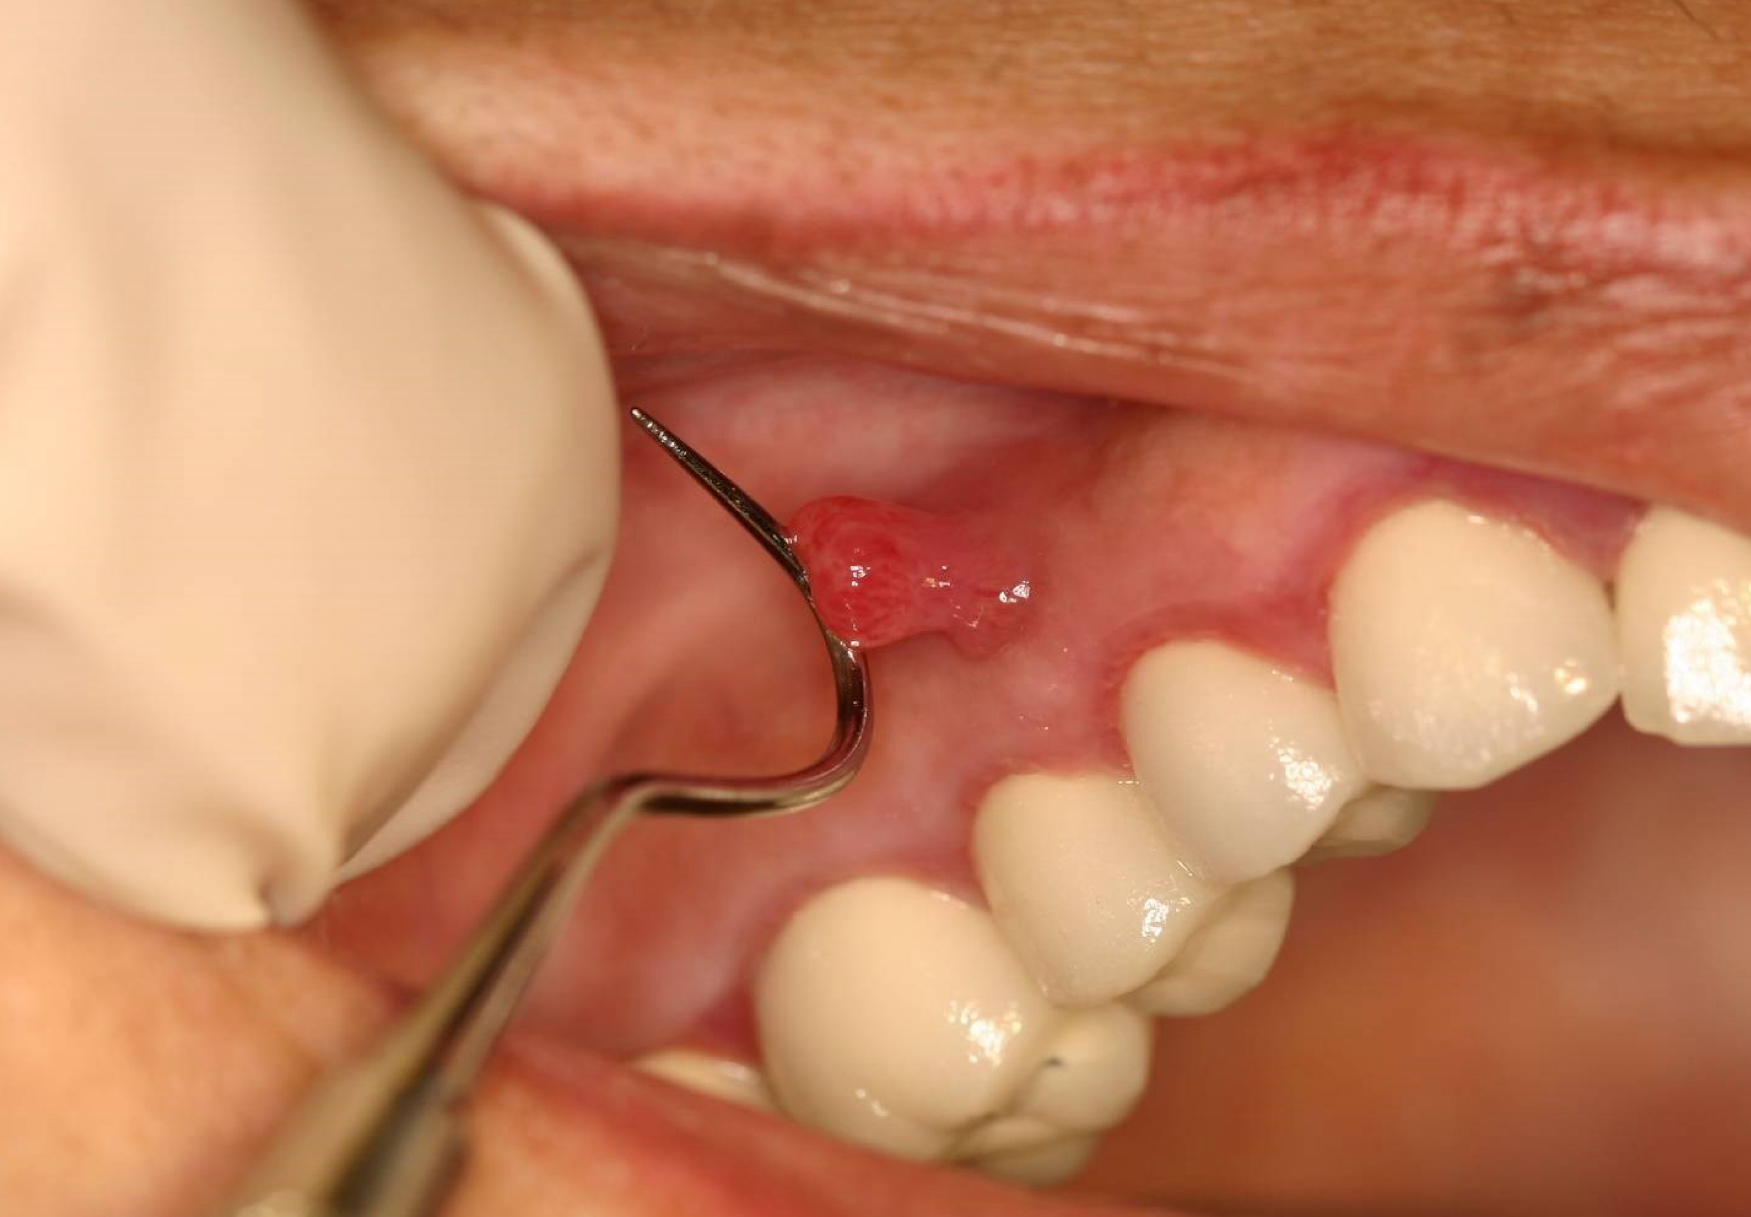

parulis aka gum boil

gum boil

parulis

which potential result of periapical inflammation?

inflamed granulation tissue at intraoral opening of sinus tract

classically dome-shaped yellow-pink papule; rarely hyperplastic soft tissue mass that may mimic pyogenic granuloma or other pathology ie exophytic hyperplastic perulis on adj tooth assocxiated w non-vital tooth

usually on gingiva facial to non-vital tooth

may or may not exhibit active suppuration